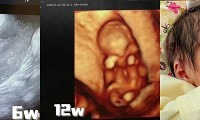

唐筛、无创、羊穿怎么选?看这篇就清楚了

1个月前 收录

阅读:3228回复:17